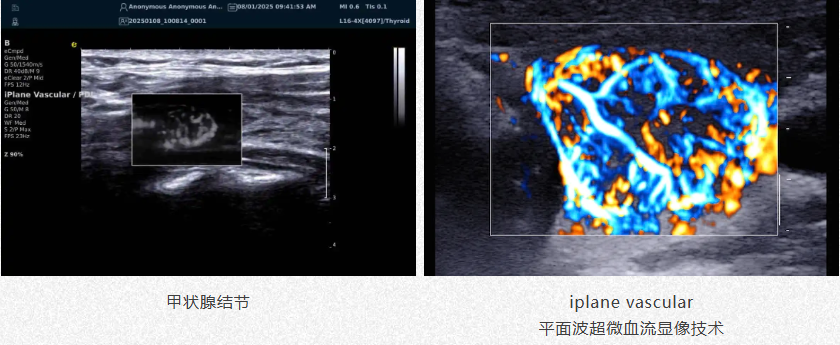

肿瘤良恶性鉴别

1.高效检测出肿瘤微细血管与低速血流,帮助医生早期发现肿瘤并进行良恶性的鉴别诊断。

2.通过血管指数(VI)定量评估肿瘤内部血管,为诊断提供客观依据。

iPlane Vascular

平面波超微细血流显像技术

可检测50μm*级细小血管低速血流信号

*注(头发丝细度通常为70-100μm)

检查中无需造影剂,具有更强的适用性